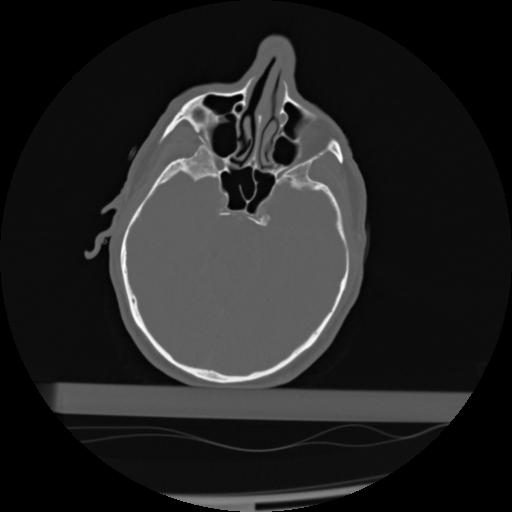

21 ANGIO,CE,Axial,3.0,ANGIO,,